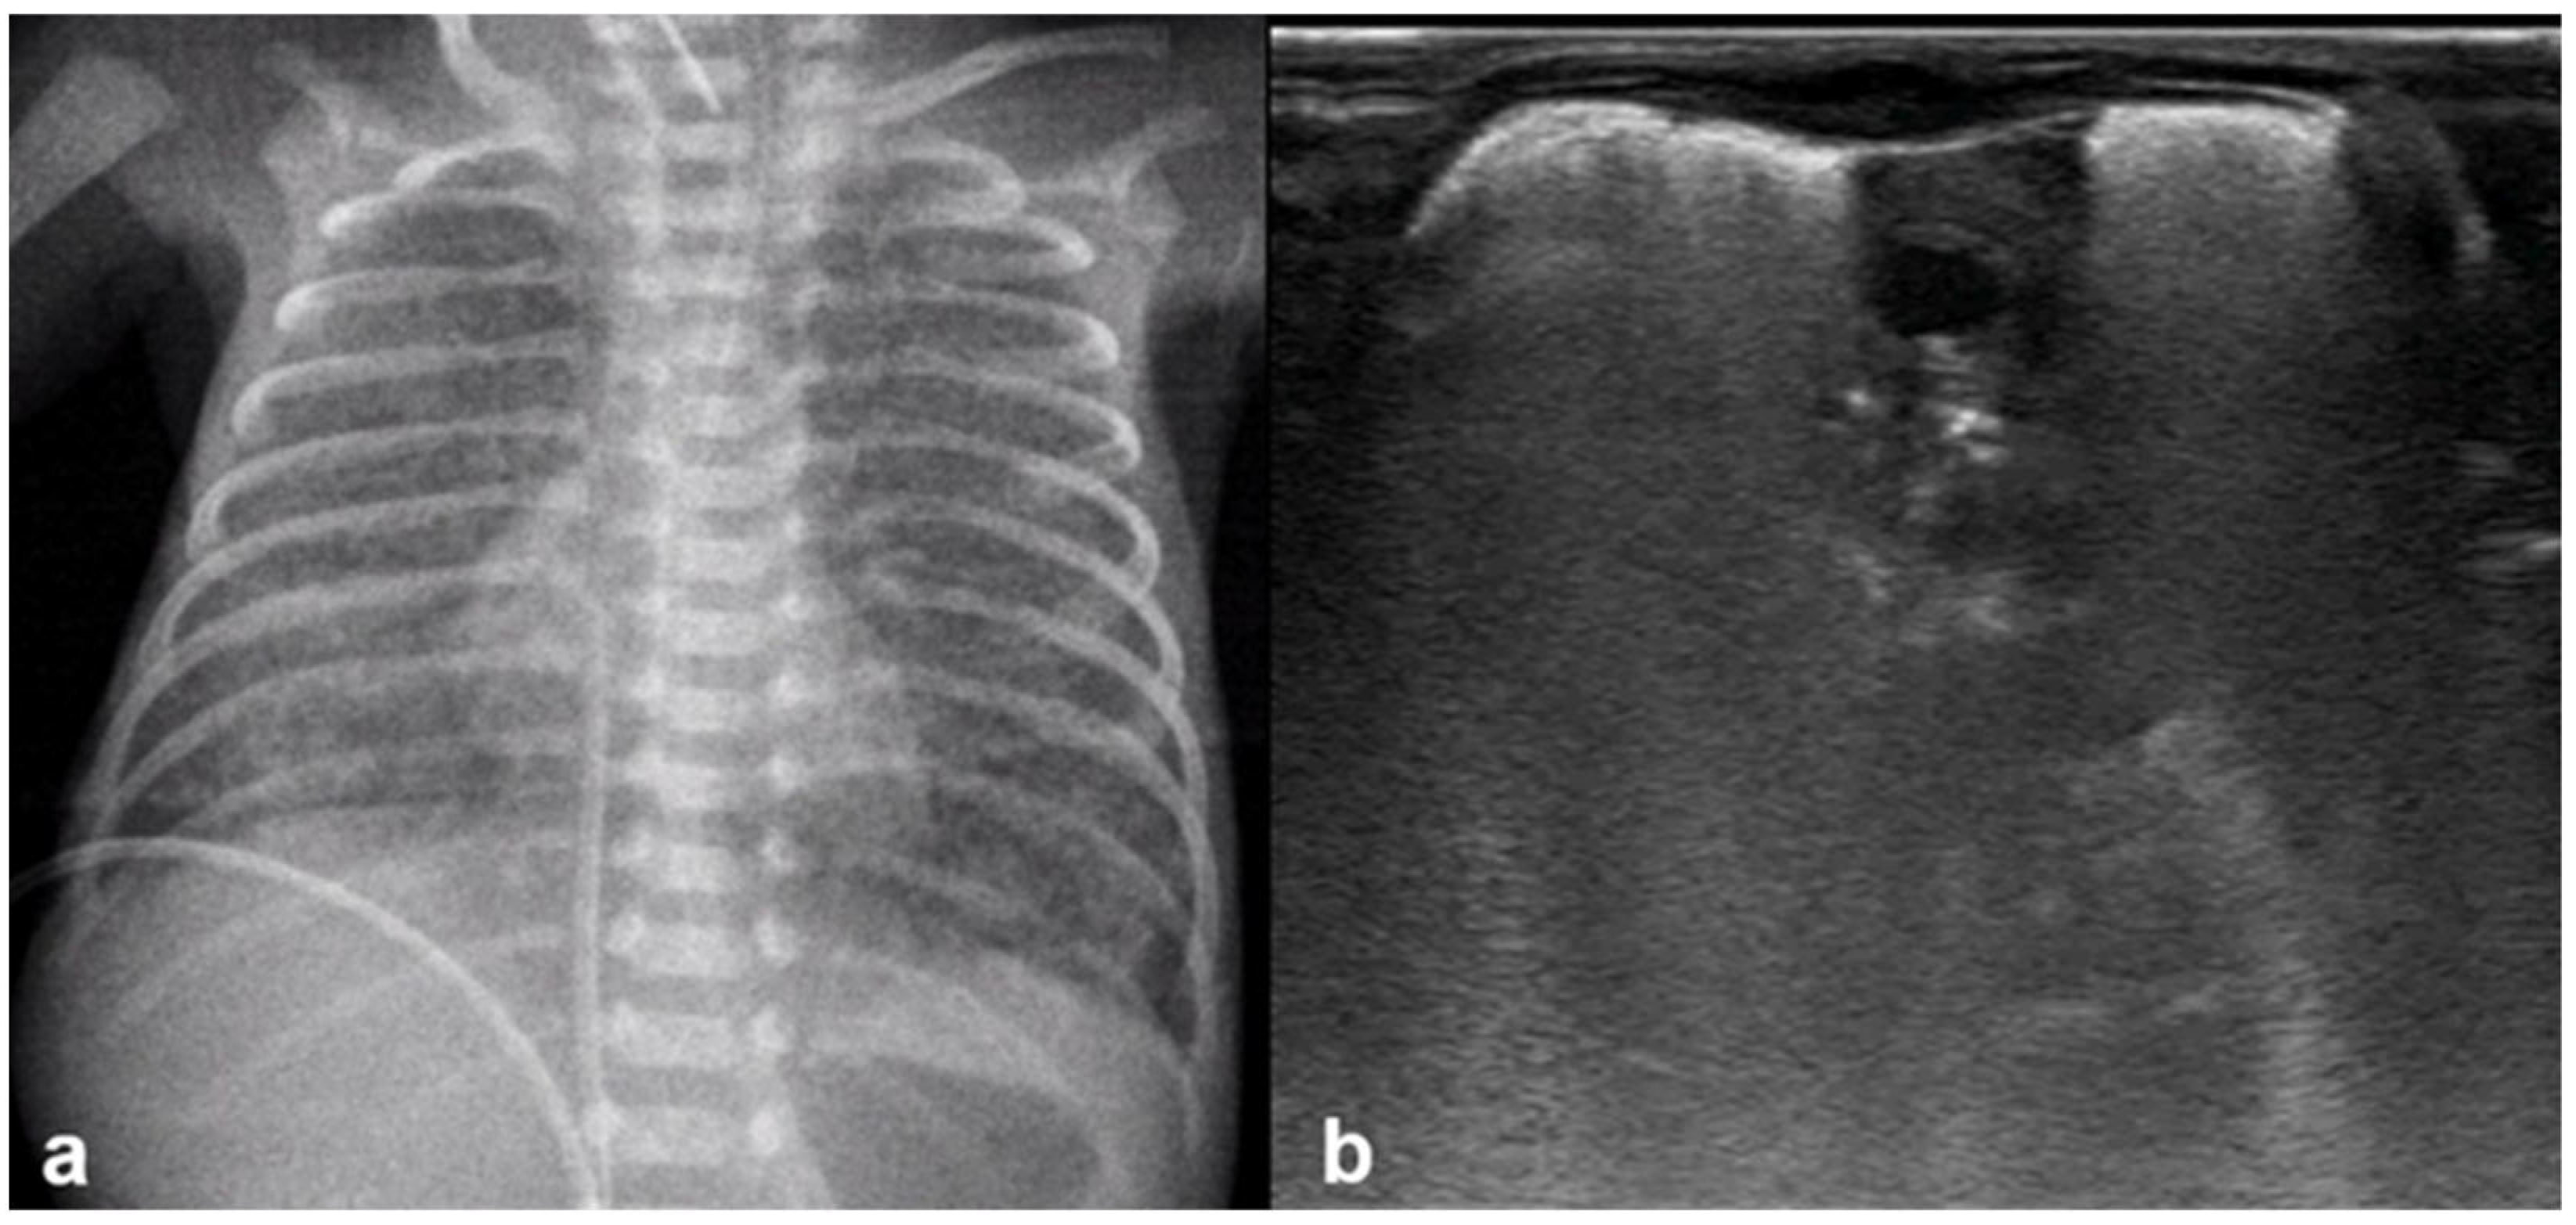

Normal to mild RDS: by chest X-ray (a); by LUS (b).

Figure 14.

Severe RDS shown on chest X-ray (a); LUS (b). The ability of the LUS to characterize the severity of the RDS is debatable.